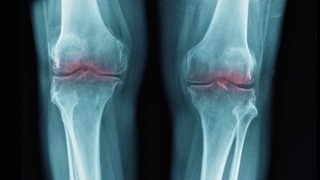

Проблема в том, что хрящ плохо восстанавливается. У него нет собственного кровоснабжения, поэтому повреждения накапливаются. Причём скрытые повреждения коленей после 30 встречаются гораздо чаще, чем кажется, даже у людей без явной боли. С годами хрящевая ткань истончается, синовиальной жидкости становится меньше, а суставы начинают болеть и терять подвижность. Этот процесс и называется остеоартритом (или остеоартрозом — в русскоязычной медицине термины используются как синонимы).

По данным масштабного анализа Global Burden of Disease Study 2021, опубликованного в журнале The Lancet Rheumatology, остеоартритом страдает около 595 миллионов человек — это примерно 7,6% населения Земли. Чаще всего поражаются коленные, тазобедренные суставы и суставы позвоночника. Причём с 1990 года заболеваемость выросла более чем на 130%.

С возрастом суставы могут становиться скованными и болезненными, что может быть симптомом остеоартрита